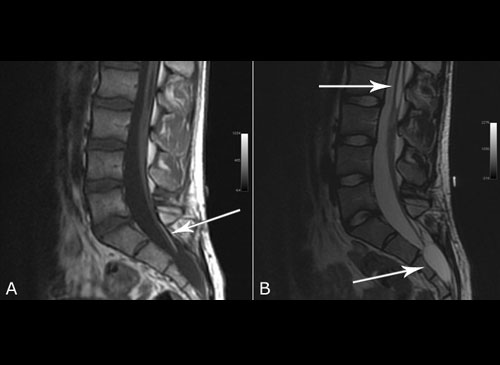

Spinal tumor

Sobti Neuro Hospital routinely does surgeries of spinal tumours with the neurosurgical microscope. A spinal tumor is a growth of cells (mass) in or surrounding the spinal cord. Surgery is needed to relieve compression on the spinal cord. These tumors are completely removed. The symptoms seen are due to spinal nerve compression and weakening of the vertebral structure. Symptoms of spinal cord compression include weakness in arms and legs, sensory loss, gradual onset paralysis and incontinence of bowel and bladder.